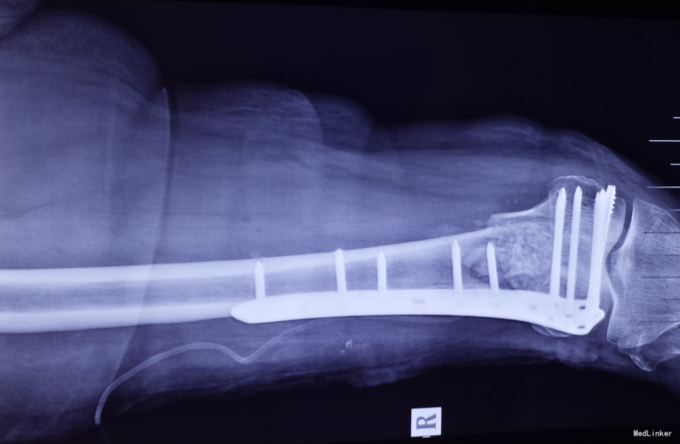

光片诊断患者骨折端粉碎,软组织损伤,发生股骨踝间骨折。采用切开复位,普通钢板、髁部支撑钢板内固定治疗股骨髁间粉碎性骨折。

股骨踝间骨折予以L型髁钢板、髁支持钢板、普通钢板加骨栓、克氏针、外固定支架固定治疗效果良好。 在恢复过程中不要吃生冷、刺激、茶叶白酒、饮料容易造成骨质疏松的食品和饮料、也不要吃猪肉等寒性食物以免影响血液循环、留下后遗症。功能锻炼越早越好。它可以促进血液循环,减少肌萎缩,消除软组织肿胀,防止骨质疏松,加快骨折愈合。